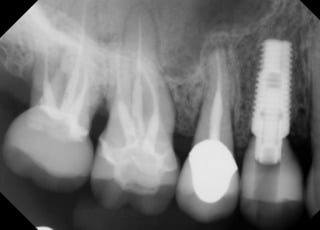

Anthony A.

This patient had only a few remaining infected teeth, but didn’t want to settle for just a denture.  Placed multiple implants and provided a secure fixed option which allowed him to not only chew better but to smile again.